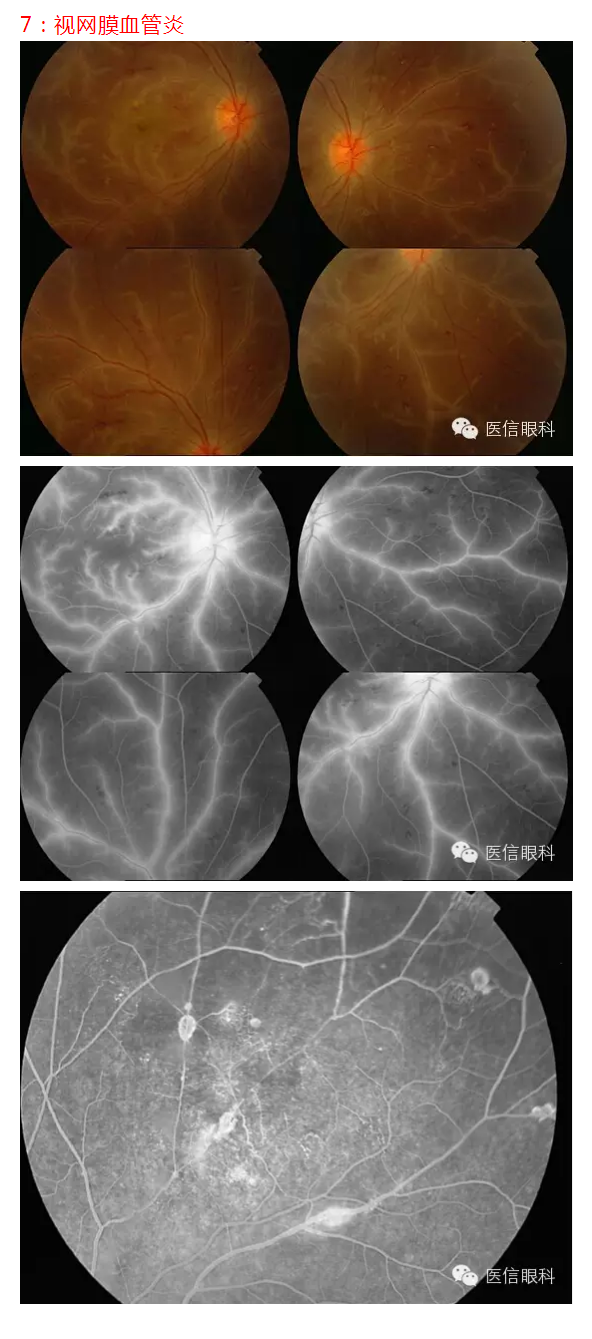

常见眼底病荧光血管造影表现(多图一)